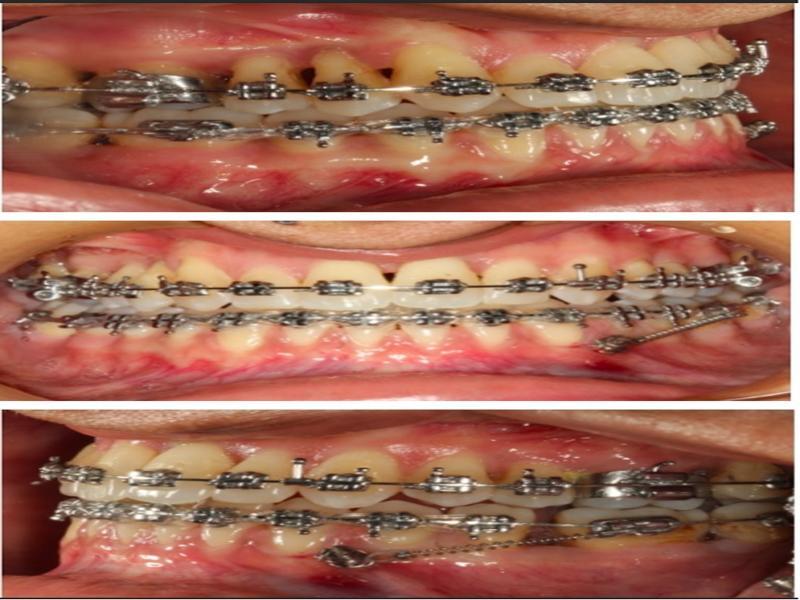

Figure 4.